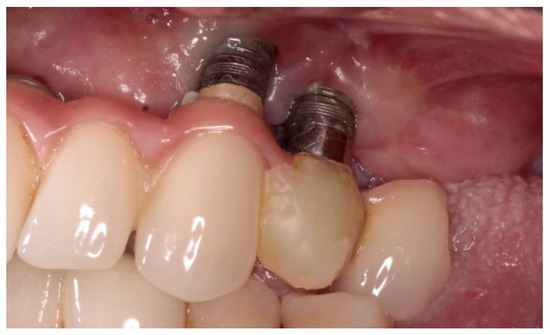

Retrospective Study of the Association between Peri-Implantitis and Keratinized Mucosa

- The presence of KM around the implants seems to have been associated with peri-implantitis and with a transparency of the peri-implant tissues.

- The absence of KM appears to have an impact on certain clinical parameters: Recession is augmented in implants with absence of KM; hygiene is facilitated when implants are surrounded by KM, therefore the plaque index is lower; probing depth tends to increase in implants without KM; bleeding and suppuration are reduced in the presence of KM and bone level tends to be lower in implants without KM.